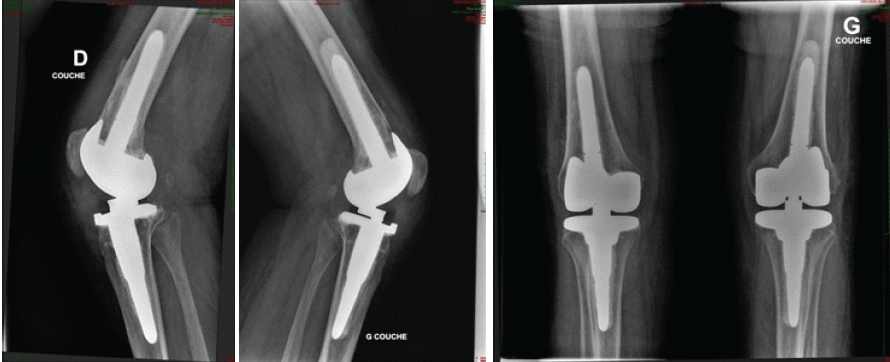

The post-operative course was satisfactory: the patient regained full extension and 90° of flexion at 6 months, without extensor lag or wound complications. She recovered independent ambulation with the use of canes at 1 year (Fig. 2).

Figure 2: Post-operative X-ray.